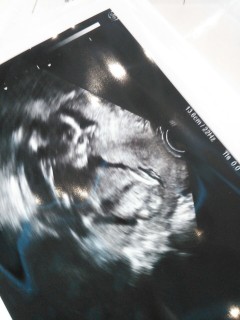

先生が「これが顔ですね~」と言うと、聞こえているのか、サッと隠して…先生と笑っていました。

その後は、お腹の中で足を伸ばしてくつろいで、頭をぽりぽり掻いていました(笑)

正面をうつしたとき、手を振っていました。AC=9.67cm